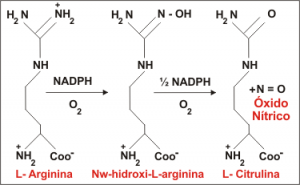

Suplementación con L-citrulina

La L-citrulina se ha propuesto como un suplemento eficaz para mejorar la producción de óxido nítrico intracelular (NO), incluso de